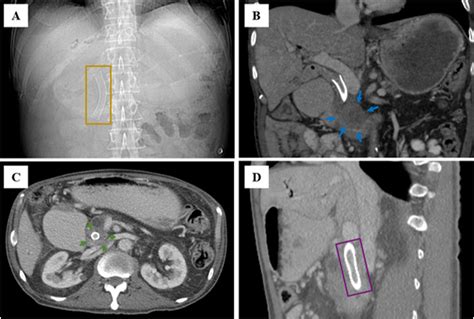

These devices are primarily inserted via a procedure known as Endoscopic Retrograde Cholangiopancreatography (ERCP). During this minimally invasive procedure, a gastroenterologist uses an endoscope—a flexible, lighted tube with a camera—to navigate through the esophagus and stomach into the small intestine, reaching the opening of the bile duct to deploy the stent.

• Imaging: Using fluoroscopy (real-time X-ray), the doctor identifies the exact location of the blockage.

• Deployment: Once the location is identified, the stent is advanced through the endoscope and expanded within the narrowed area of the bile duct.

• bile duct stent ct